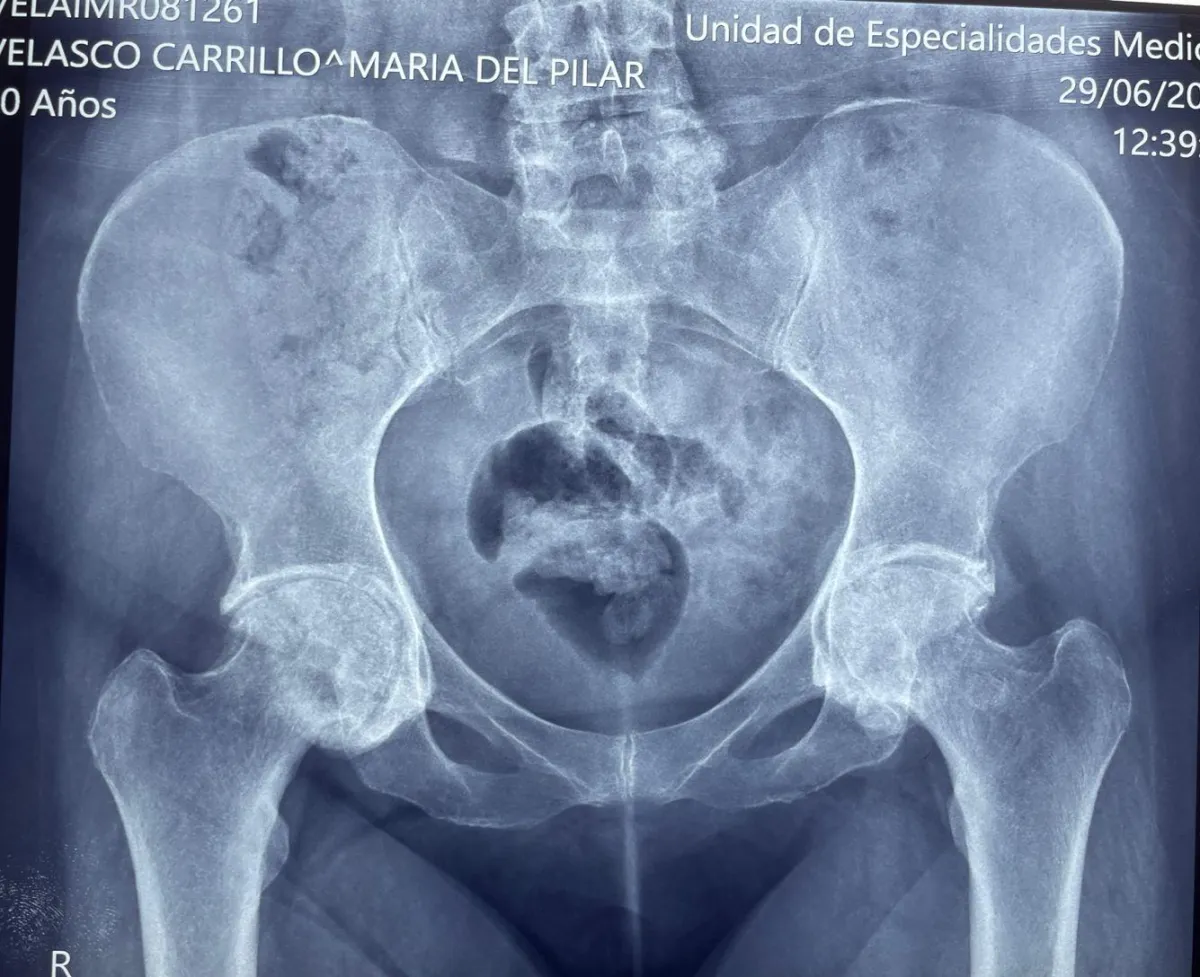

Prótesis de Cadera

Complicación manejada con prótesis de doble movilidad

Paciente al segundo día postoperatorio. Complicación abordada mediante colocación de prótesis de doble movilidad.